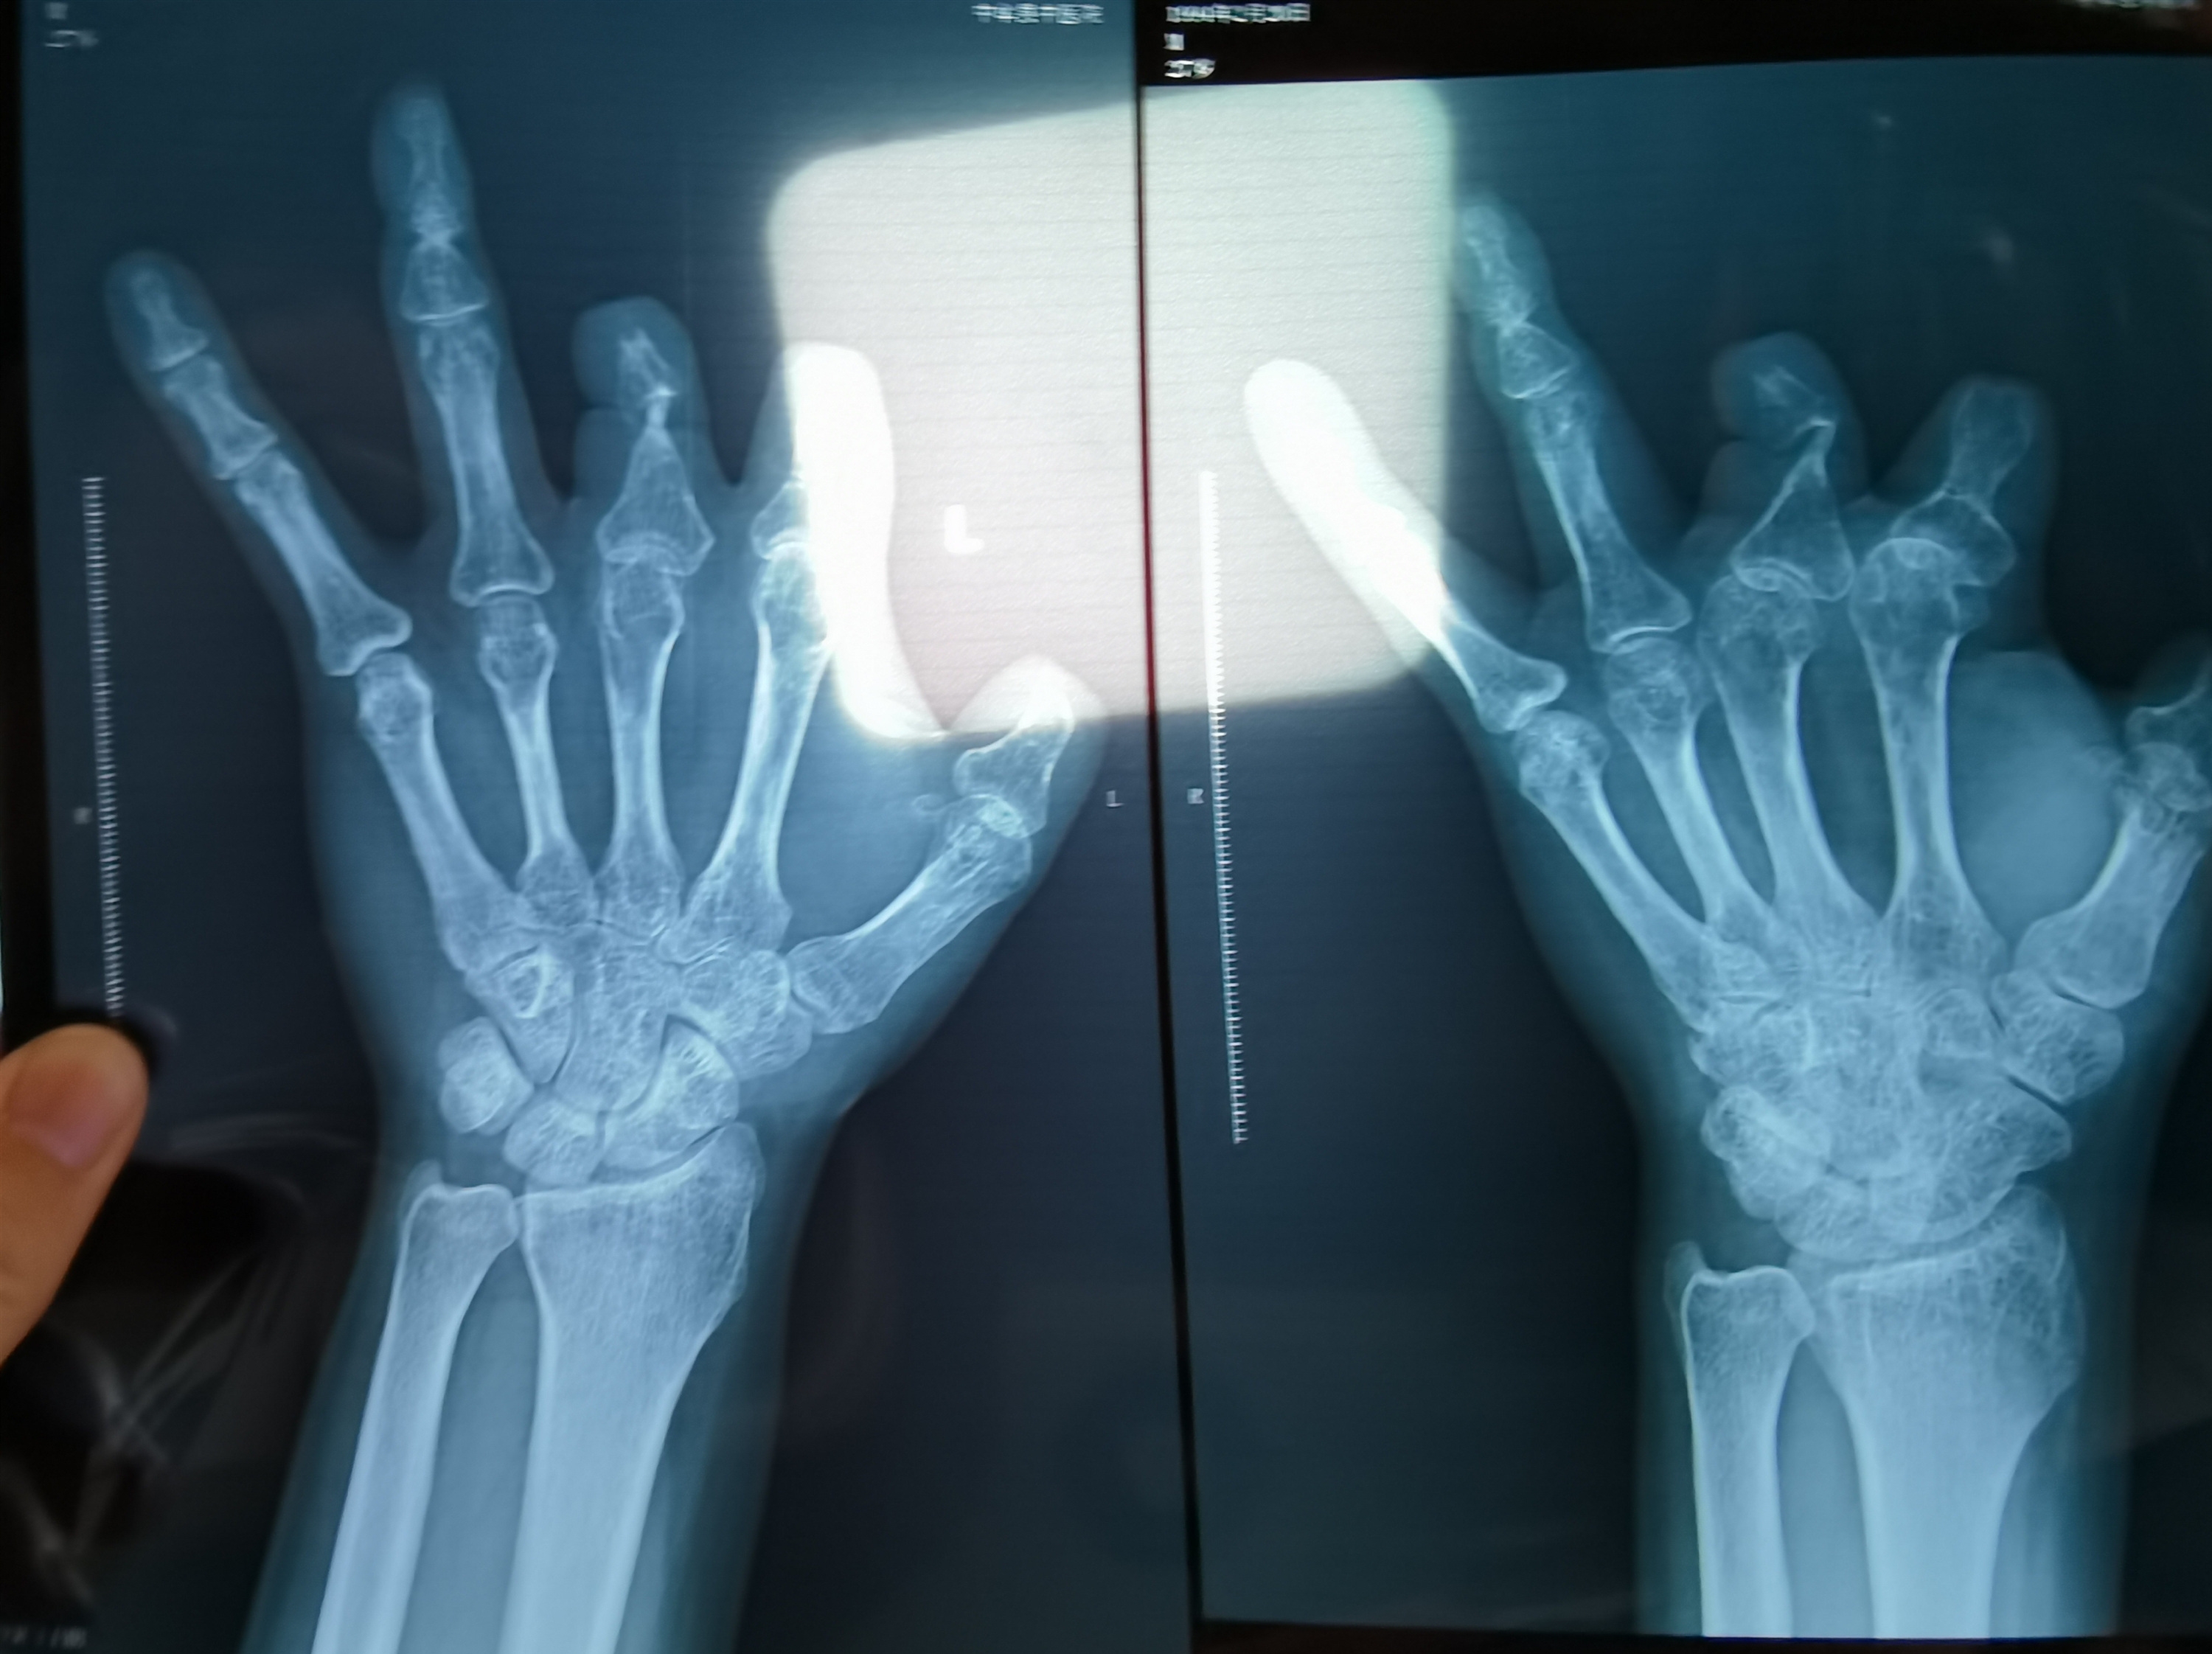

患者王海森左手拇指关节以上部位被电锯切断,收费单显示术中使用了微血管吻合装置,但X光片中未显示该器械。新京报记者程亚龙摄

单价1.68万元,声称在术中植入体内、用于缝合血管的两个环形吻合装置,竟然在王海森的X光片上消失了。

装置上带有不锈钢针,不可能被人体吸收,唯一的可能就是“手术时其实没有使用”。尽管之前也有其他人向王海森透露过这一点,但直到看到片子前,他一直都不相信。

王海森称,他出院约1年后,有人曾找到他说,这个价格昂贵的进口器材,并没有在手术中使用。当时他没有相信,直到2021年12月,经人提醒,王海森在老家开封尉氏县人民医院拍摄了左手X光片,才确认手术部位的确没有微血管吻合装置。2021年12月底,王海森向郑州市公安局二七分局刑侦大队报案。

2021年12月,患者彭先生拍摄的左手X光片,未见收费单据中列出的微血管吻合装置。新京报记者程亚龙摄